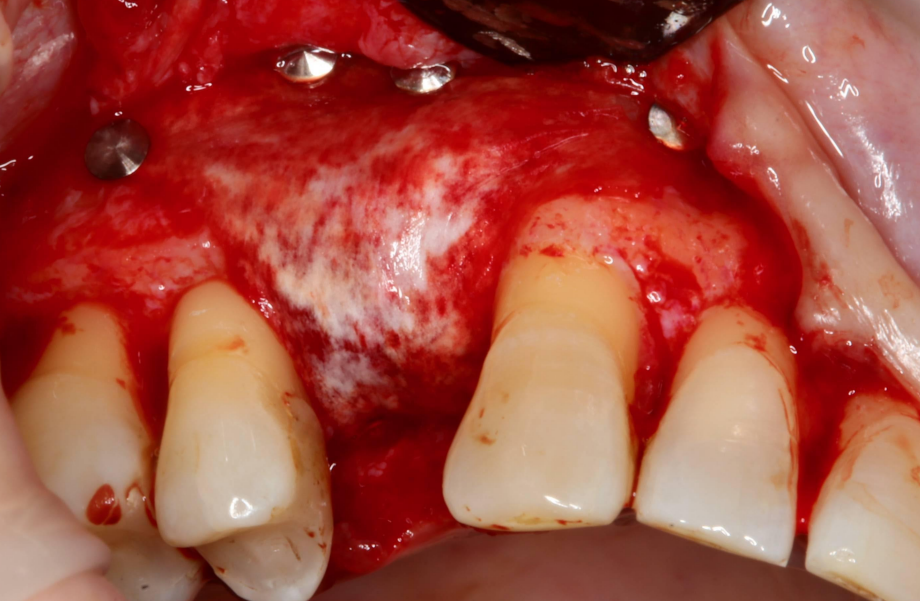

Szkolenie koncentruje się na przewidywalnych i bezpiecznych technikach augmentacji, w tym horyzontalnej i pionowej regeneracji kości, z dużym naciskiem na praktykę – uczestnicy wezmą udział w trzech warsztatach na preparatach zwierzęcych oraz zabiegach pokazowych (wideo), obserwując pracę doświadczonych wykładowców krok po kroku.

11:45 – 12:30 – Projektowanie płata i zarządzanie tkankami miękkimi podczas regeneracji kości.

12:30 – 14:00 – Warsztat. Projektowanie płata, jego mobilizacja oraz właściwe szycie. (preparaty zwierzęce).

15:00 – 16:15 – Technika „Sausage Technique” jako złoty standard w horyzontalnej regeneracji kości – zasady oraz Tips&Trics.

16:30 – 18:00 – Warsztat, Technika Sausage (samodzielne wykonanie zabiegu na preparacie zwierzęcym).

9:30 – 11:30 – Zabiegi na żywo lub VIDEO z zabiegów regeneracji kości.